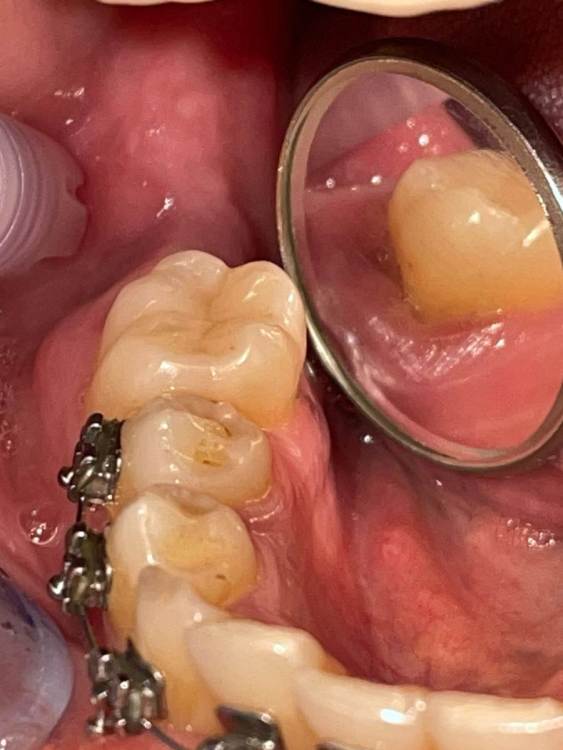

Graf Опубликовано 26 августа, 2023 Поделиться Опубликовано 26 августа, 2023 Пациентка пришла с жалобами на пульсирующие боли и небольшую опухлость в области 46 зуба. Что можете сказать по данному случаю и есть ли возможность сохранить этот зуб? Ссылка на комментарий

Жандос Муратович Опубликовано 29 августа, 2023 Поделиться Опубликовано 29 августа, 2023 Удалите его, чем быстрее тем лучше 1 Ссылка на комментарий